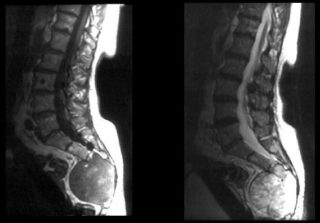

- Как правило, диагноз на основе рентгенографии, МРТ или КТ. Также врач прощупывает опухоль, определяя ее границы и консистенцию — они имеют значение для постановки диагноза.

При появлении шишки на позвоночнике необходимо выяснить причину, пройдя обследование

УЗИ позволяет установить принадлежность опухоли к доброкачественным или злокачественным новообразованиям

Перед назначением эффективной схемы лечения врач проводит осмотр и опрос пациента, выясняя детали: время появления, увеличение, общее самочувствие, наличие температуры. К обязательным обследованиям относятся:

- лабораторная диагностика – общий и биохимический анализ крови, анализ на онкомаркеры;

- УЗИ, которое позволит установить основные параметры опухоли;

- КТ или МРТ назначаются при подозрении на метастазы;

- биопсия необходима для исключения злокачественной опухоли.